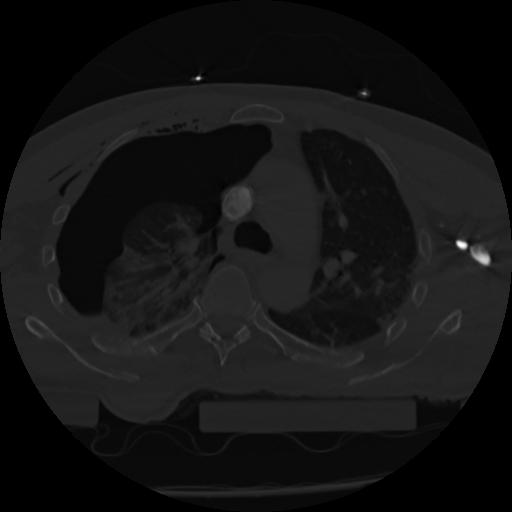

22 ANGIO,CE,Vol,0.5,ANGIO,,